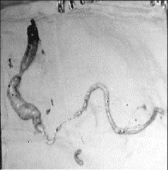

Resultó que la paciente tenía un tumor que nacía en la zona de la ingle izquierda y se extendía por la vena cava inferior hasta las cavidades derechas (aurícula y ventrículo) del corazón. Medía un metro 46 centímetros de largo, 3.5 centímetros de diámetro y un peso de 300 gramos.

Los médicos "aislaron" con una cinta la vena cava y realizaron una incisión por donde extrajeron la totalidad del tumor. El control médico posoperatorio es favorable hasta ahora, y según el experto en unos cuantos días Rosa María Padilla podrá regresar a su hogar.